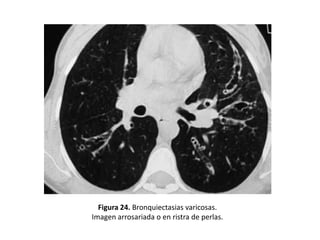

• Varicosas:

– Los bronquios presentan dilataciones irregulares

– Alternando zonas de dilatación con zonas de

constricción localizadas y terminación bulbosa

– Aspecto arrosariado o en “ristra de perlas” cuando

el bronquio afectado transcurre horizontal al

plano de corte (Figura 20 y 24).

Figura 24. Bronquiectasias varicosas.

Imagen arrosariada o en ristra de perlas.

• Los distintos tipos morfológicos se correlacionan

con la severidad de la enfermedad (las varicosas y

quísticas son manifestación de una enfermedad

más avanzada).

• Pacientes con BQ quísticas presentaban con más

frecuencia esputos purulentos, colonización por

Pseudomonas aeruginosa y mayor alteración de

los parámetros espirométricos que los pacientes

con BQ cilíndricas o varicosas.